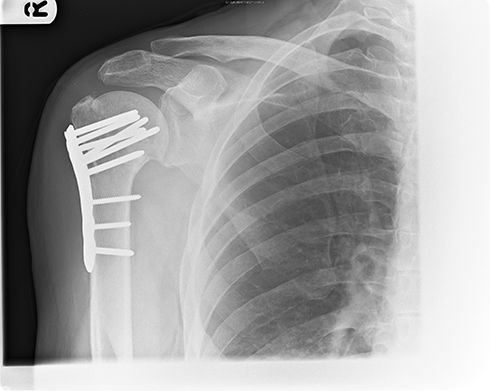

In 2009, on my birthday, I shattered my right humerus while walking to my car after work; uneven ground, an armful of presents from friends, an SUV parked where it shouldn’t have been and my natural clumsiness meant that I was probably destined to lose my balance at some point (my youngest brother broke his leg while walking in his yard; we’re all clumsy and breakable).

“Humerus,” tracked to the 15th century, means the long bone of the upper arm from the shoulder to the elbow, and comes from the Latin “umerus,” meaning upper arm or shoulder. My break was a proximal break, meaning near the shoulder (it actually separated from the shoulder, fun); had it been close to the elbow, it would have been a distal break. It was also comminuted, where the bone breaks or splinters into more than two pieces; mine was in four big pieces with various splinters, so I had to have surgery to repair it with titanium pins and a plate, and to replace some bicep tissue that was destroyed.

But why “funny bone”? Is it just because “humerus” and “humorous” are homophones? Well, yeah, but “funny bone” doesn’t even really refer to the humerus, but rather the ulnar nerve that rests between the point of your elbow and the humerus’ medial epicondyle. Hitting that nerve is a painful experience for most people.

Breaking your humerus isn’t much fun either.